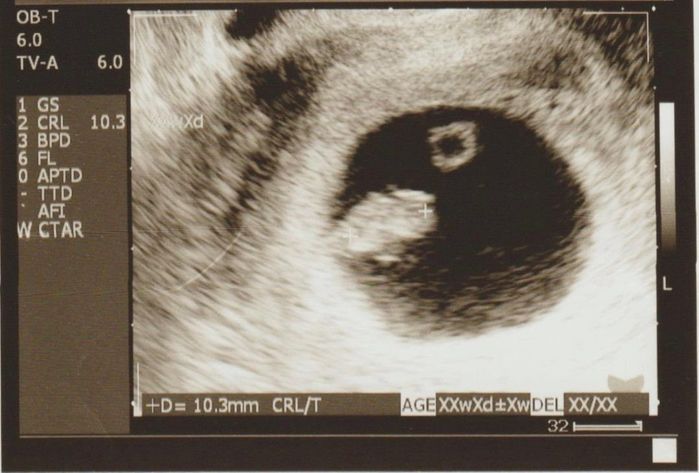

心拍が確認できる - 妊娠7週目のエコー写真

D=10.3mm 心拍が確認できる

心拍が初めて確認できました。この2週間、正直流産の不安の方が大きくて、「ちゃんとおなかの中で元気かな? 」と心配ばかり。先生から「心臓が動いているの見える?」と言われた時には、「本当に私のおなかの中に命が宿っているのだな」と、初めて実感が湧いてきて、「元気に育ってね!」「この子は絶対に産むんだ」という強い思いも湧いてきました。